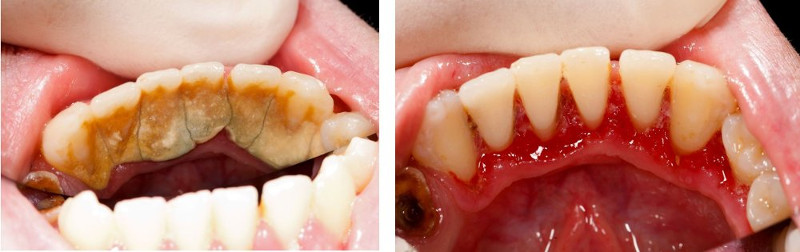

Зубные отложения делятся на неминерализованные и минерализованные. Неудовлетворительная гигиена полости рта приводит к тому, что пищевые остатки образуют очень стойкую к разрушению биопленку и зубные бляшки, а так же накопление мягкого зубного налета и его постепенное распространение на поверхности зуба. Под воздействием микрофлоры полости рта, продуктов их распада происходит постепенная минерализация зубного налета и его превращение в твердый зубной камень. По месту расположения различают два вида зубного камня: наддесневой и поддесневой. Сначала образуется наддесневой зубной камень, который за короткое время разрушает зубо-десневое прикрепление и начинает формировать поддесневой зубной камень, который интенсивно растет внутрь по корню зуба, разрушая связочный аппарат пародонта, впоследствии, образуется зубо-десневой карман — промежуток между десной и зубом, далее — костный карман и, как следствие всего этого, выпадение зуба. Зубные отложения очень способствуют фиксации и размножению микроорганизмов, что еще более затрудняет самостоятельное удаление налета пациентом.

Врачи-стоматологи рекомендуют проводить профессиональную гигиену полости рта не меньше двух раз в год. Количество приемов зависит от индивидуальных особенностей организма и состава слюны. Основная задача стоматолога убрать стойкую биопленку, неминерализованные зубные отложения. Гигиена, проведенная специалистом, также способствует устранению налета от красящих напитков, продуктов, курения, неприятного запаха в результате всех вышеперечисленных негативных воздействий. После чистки, естественный тон зубов становится светлее, а пациенты отмечают ощущение свежести в ротовой полости.

Затем при помощи специальных наконечников (скейлеров)

и ультразвука

доктор снимает минерализированный зубной налет, при этом эмаль зубов не травмируется, как считают некоторые пациенты и отказывают себе в подобных процедурах, что влечет за собой негативные последствия. Далее, в комплексный подход к профессиональной гигиене, обязательно включен воздушно-абразивный метод обработки зуба или Air Flow,